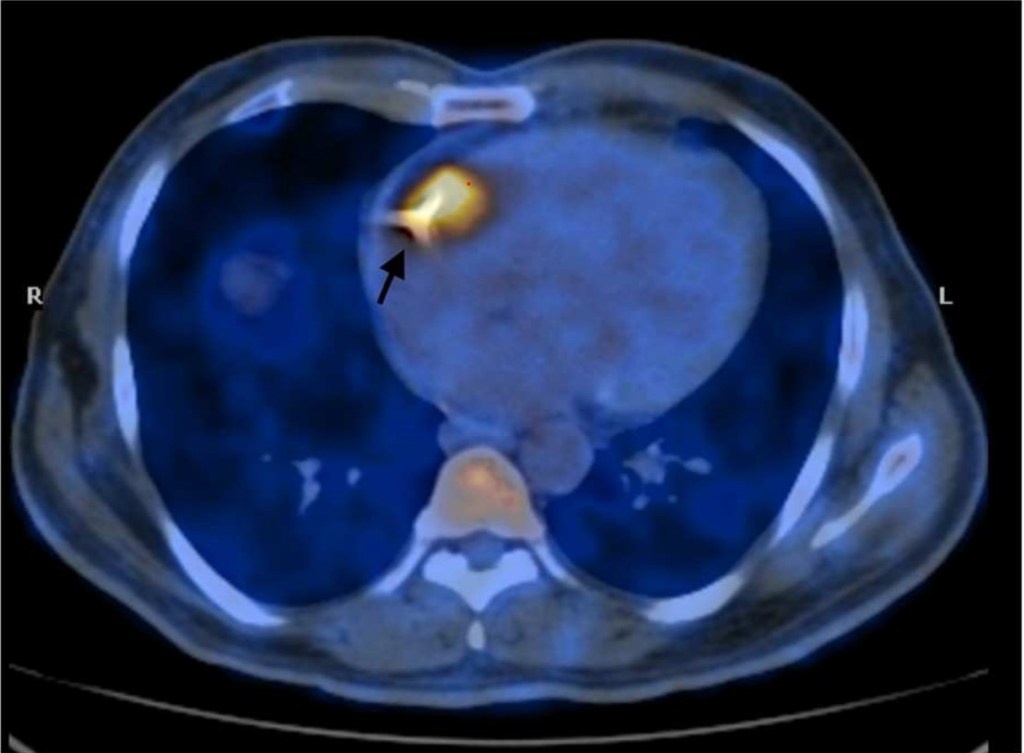

It is an afterthought, I think, from the makers of annular restriction device makers. MEER is found to be less effective in proportional MR.The Carillon device is a new arrival to tackle secondary MR .It is actually a wire that forcibly tightens the AV annulus inserted through coronary sinus . This modality takes advaantage of the aantomical proximity of coronary sinus to mitral annulus. Coronary sinus encircles and from a virtual wall along significant circumference of mitral annulus.